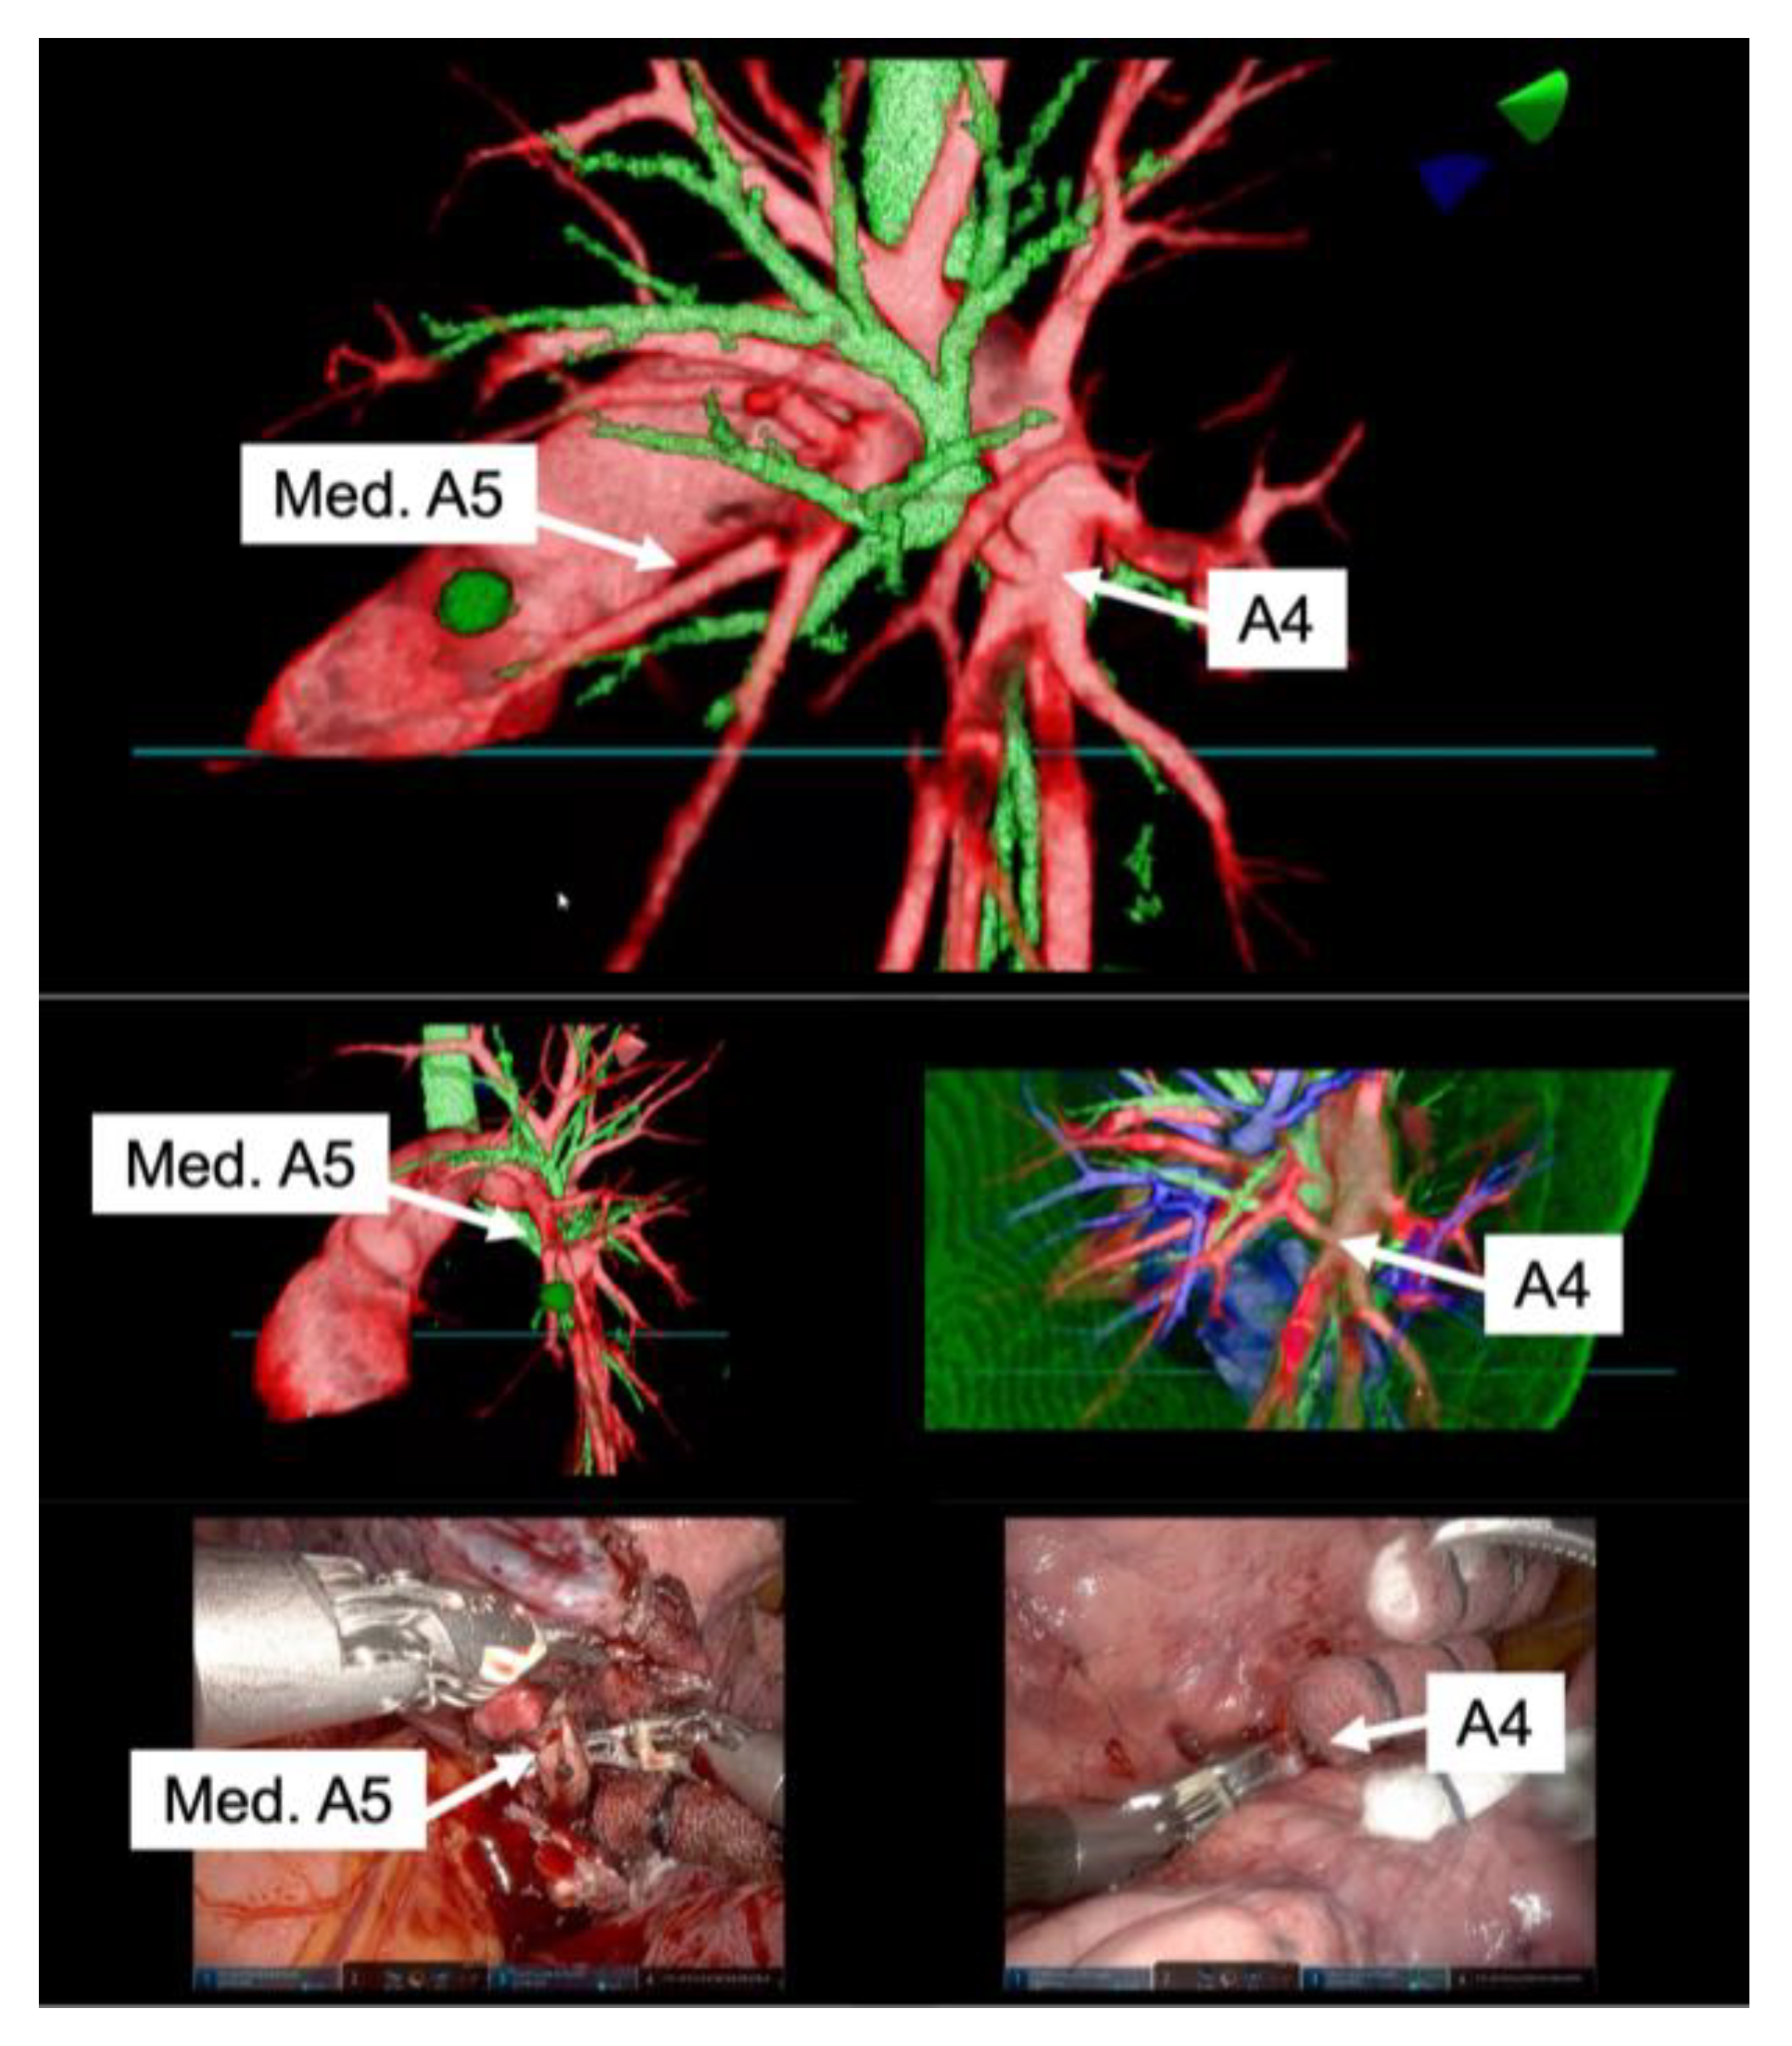

High-resolution anatomical details of the subsegmental pulmonary artery branches were clearly visualized in the representative images of the 3D model. This detailed visualization was crucial in confirming the orientation of the vessels intraoperatively, both before and after vessel ligation, as depicted in Figure 3. The specific case of left lingular segmentectomy involved the resection of a 15 mm nodular lesion in the left segment 4 + 5. The preoperative preparation with the VR HMD was instrumental in identifying a variant in the PA vessel anatomy, specifically a mediastinal branch A5 (Med. A5) (Figure 4).

Figure 4.

Correlation between preoperative reconstruction and intraoperative findings. The top row of representative images from the 3D model showcases high-resolution anatomical details, including the variant branches such as the mediastinal branch A5 (Med. A5) and the interlobar branch A4. The bottom row of images presents intraoperative views, confirming that the orientation and structure of the pulmonary artery branches, as visualized in the 3D model, were accurately represented.